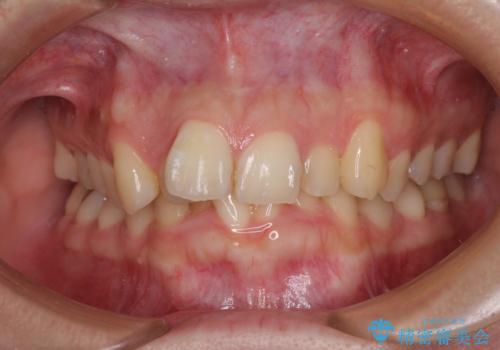

前歯のデコボコを治したい インビザラインによる矯正治療

- 上下前歯のデコボコを気にして来院された患者様です。

インビザラインによる上下歯列の側方拡大と後方移動、IPR(歯と歯の間を削る)にるスペースの獲得により歯列を整えることとしました。

1日22時間の装着時間をしっかり守ってくださったので、予定していた1年よりも早く治療を終えることができました。

インビザライン矯正特有の奥歯がしっかりと咬合しない感覚も改善され、大変満足していただきました。